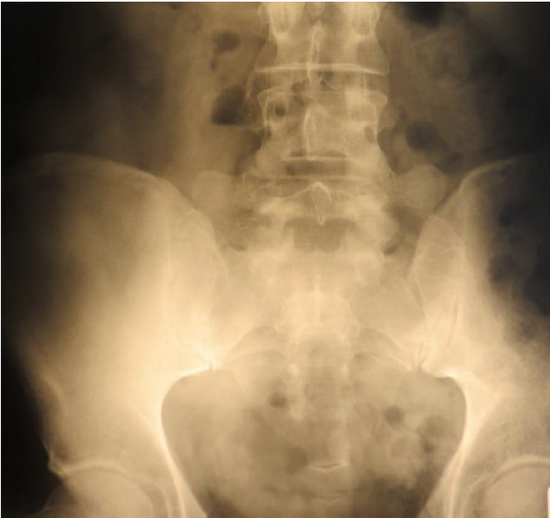

Dans la fameuse situation de lésion ostéopathique vertébrale que nous connaissons tous, sur la photo, c’est l’opérateur qui maintient artificiellement L2 et L3 en position de latéroflexion droite, mais dans le corps, le seul tissu qui peut maintenir obstinément cette anomalie de façon active et permanente ce sont les fascias, les tissus fibreux y compris ceux des muscles , le filet fibreux (épipysium et périmysium, peut-être l’endomysium) qui parcourt l’intégralité des masses musculaires.

La nature insaisissable radiologiquement de la lésion est due au fait que celle-ci ne s’exprime que dans le cadre du mouvement articulaire, mais ne se contracte pas au repos, donc à la radio.